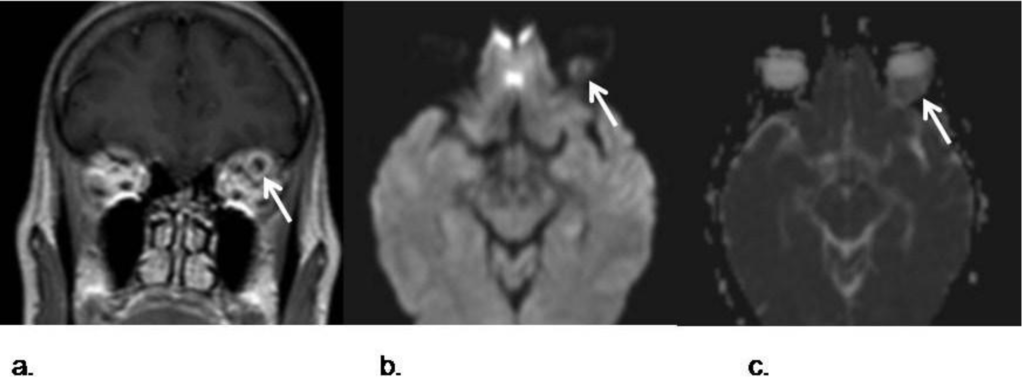

- Viets, R.; Parsons, M.; van Stavern, G.; Hildebolt, C.; Sharma, A. Hyperintense optic nerve heads on diffusion-weighted imaging: a potential imaging sign of papilledema. AJNR Am. J. Neuroradiol. 2013. [Google Scholar] [CrossRef]

- Fatima, Z.; Motosugi, U.; Muhi, A.; Hori, M.; Ishigame, K.; Araki, T. Diffusion-weighted imaging in optic neuritis. Assoc. Radiol. J. 2013, 64, 51–55. [Google Scholar] [CrossRef]